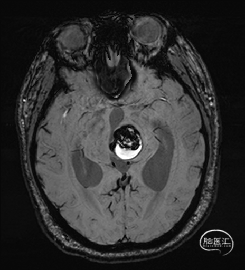

术前MRI检查

术前MRI检查提示左侧丘脑中脑海绵状血管瘤并卒中,梗阻性脑积水;

根据MRI及DTI显示,只有在丘脑与上丘之间的点(dot)进入病变才可能在切除病变时最大程度保护神经功能,由于上述原因,该“点”在术中显露极其困难,虽有导航指引,电生理监测的条件下,对术者的耐心、技术、经验及体能依然是极大的挑战;

术前详细的磁共振检查,包括平扫增强,SWI及DTI,可以规划出手术最适宜的路径及切入点;